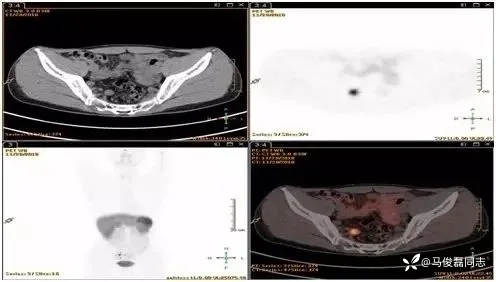

8、直肠神经内分泌瘤需要做68镓-PET-CT或奥曲肽扫描么?

答:直径小于1cm,CT或MRI检查无可疑转移病灶的,可以不做;直径超过1cm,CT/MRI等影像检查有可疑结节或病灶的需要做。

9、肠周发现几毫米的淋巴结有可能是转移么?

答:目前研究认为,直肠NET出现肠周淋巴结超过5mm,80%的可能性是转移的,因此出现这种淋巴结建议做生长抑素受体显像进一步明确。